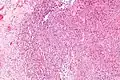

| Micrograph of an epithelioid sarcoma. H&E stain. | |

Histologically, epithelioid sarcoma forms nodules with central necrosis surrounded by bland, polygonal cells with eosinophilic cytoplasm and peripheral spindling.[3] Epithelioid sarcomas typically express vimentin, cytokeratins, epithelial membrane antigen, and CD34, whereas they are usually negative for S100, desmin, and FLI1 (FLI-1).[3] They characteristically lack the protein INI1 (see below). Epithelioid sarcomas typically stain positive for CA125.[4]